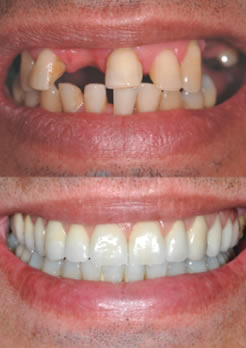

Antes – Paciente homem 45 anos, com perda de vários dentes e alteração no posicionamento dos dentes

Antes – são realizados exames pré operatórios como: exame de sangue, radiografias, tomografia computadorizadas em 3D, avaliação geral do estado de saúde do paciente e análise estética com Smile Design Pro

Antes e depois do tratamento

Antes do tratamento